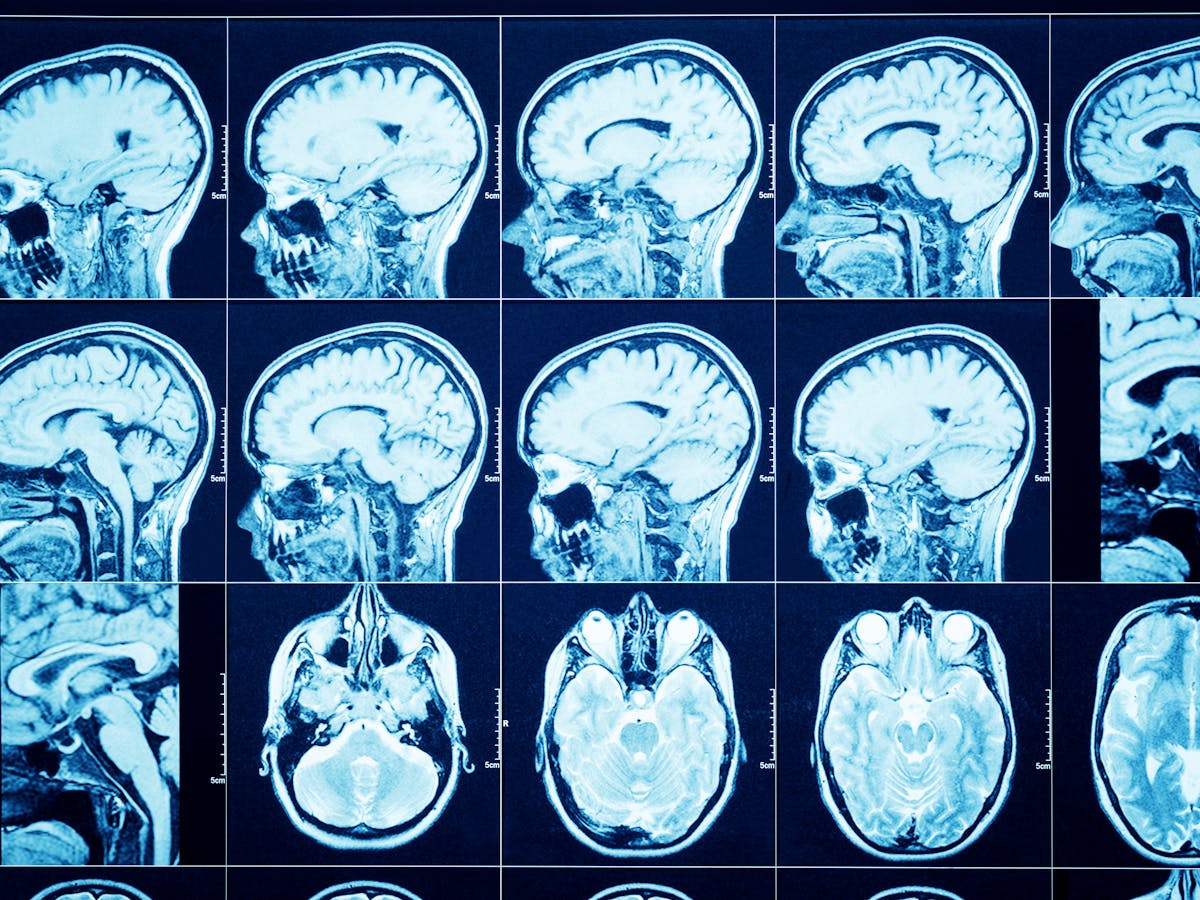

Most people with covid 19 will experience only mild symptoms especially in the early stages of the disease according to the world health organisation who. A headache isnt a common symptom of the virus but about 14 of people infected with corna have experienced it according to the report of the who china joint mission on coronavirus disease 2019. A new study published in the jama neurology medical journal shows that covid 19 may cause neurological symptoms such as headaches sometimes without the usual respiratory complications like a. Others include a runny nose sore throat nasal congestion pain diarrhoea and the.